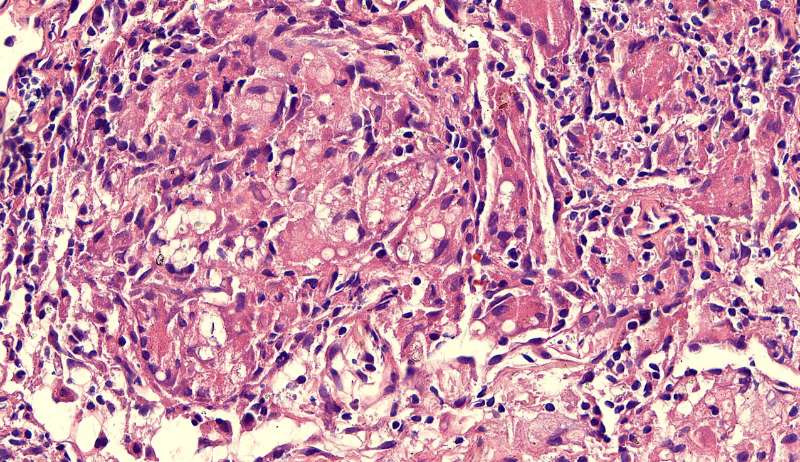

最后发一例化脓性炎症

中性粒细胞很多,此处组织结构破坏

左侧液化,脓肿壁较规则平滑

周围的炎症机化区

破坏力在这里逐渐减弱

逐渐从中性粒细胞转为淋巴细胞为主

周边区:

肺泡内有渗出,逐渐吸收 机化是不是纤维细胞增多看的?王:是的